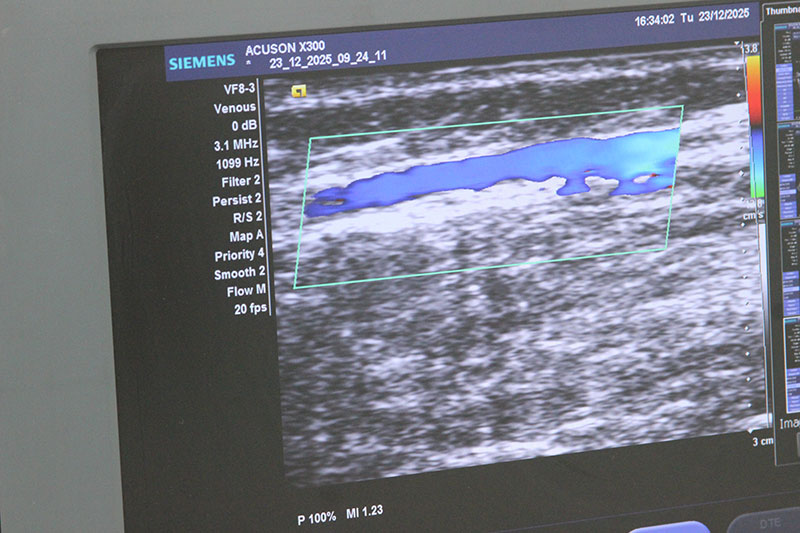

ЭХО-склеротерапия – современная методика безоперационного лечения варикозного расширения вен, сочетающая склерозирование с УЗ контролем в реальном времени. В отличие от классической склеротерапии, врач на экране видит положение иглы и сосудов. УЗИ позволяет ввести специальный препарат (склерозант) в просвет пораженной вены.